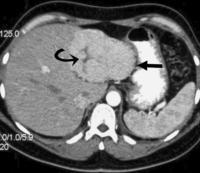

平掃FNH表現為等密度或略低密度,中心瘢痕結構呈更低密度,邊界不清或欠清。平掃表現只能發現病

灶,等密度病灶可能遺漏,更無法定性。由於隨著螺鏇CT 的套用, 可動態觀察病灶在各期掃描的強化特徵,

這使實現FNH 的術前正確診斷成為可能。(1)動脈期掃描:FNH 因富含血管,動脈期均有明顯強化且除中心

瘢痕外強化均勻一致。(2)門脈期掃描:大多數病灶為稍高密度或等密度,伴有中心瘢痕者,瘢痕未見強化;

(3)延遲期掃描:門脈期和延遲期表現為稍高密度或等密度反映了FNH的富血供的特點,為與其他肝內占位性

病變的鑑別診斷提供了幫助。 瘢痕延遲強化是FNH的特徵性CT表現。